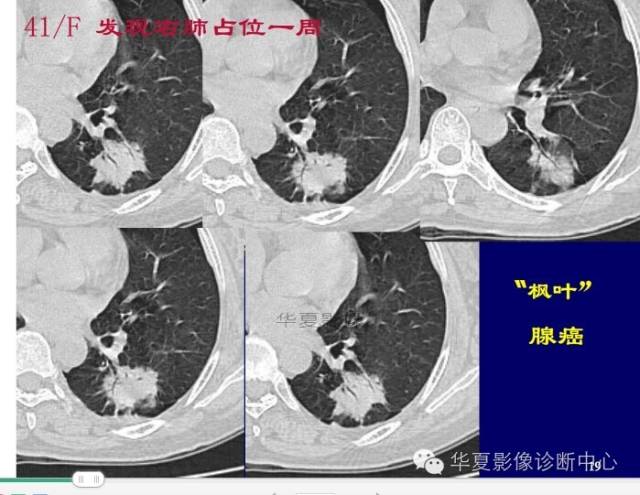

周围GGO边界清楚,分叶征、胸膜凹陷征、含气支气管,混合型GGO

磨玻璃结节良恶性影像分析策略 混合型,边界清楚、分叶征,考虑肺癌

边界清楚,分叶征,空泡征